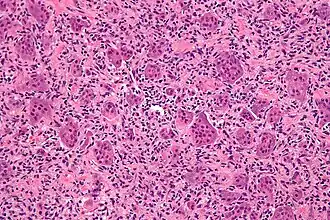

Микрофотография гигантских клеток остеобластокластомы кости, характерно выделяются гигантские клетки. Окрашено гематоксилином и эозином.

Микроскопическая структура гигантоклеточной опухоли кости, в основном, представлена двумя типами клеток. Преобладающее большинство клеточных элементов составляют веретенообразные, овальные и округлые клетки с умеренно выраженной цитоплазмой и светлым ядром, содержащим небольшое количество хроматина. В ядрах определяются одно, а иногда два хорошо различимых ядрышка, могут выявляться фигуры митоза, как правило, типичные.

Другим клеточным компонентом являются многоядерные гигантские клетки. Эти клетки очень похожи на нормальные остеокласты, но обычно несколько крупнее их и имеют закругленный контур. Они содержат 20-30 и более ядер, большинство из которых располагаются в центре клетки. Ядра многоядерных клеток обычно лежат изолировано друг от друга и, практически, не отличаются от ядер одноядерных клеточных элементов. Цитоплазма этих клеток слегка базофильна. В многоядерных гигантских клетках фигур митоза не определяется. Эти клетки равномерно (важный дифференциальный диагностический признак!) расположены в опухоли.